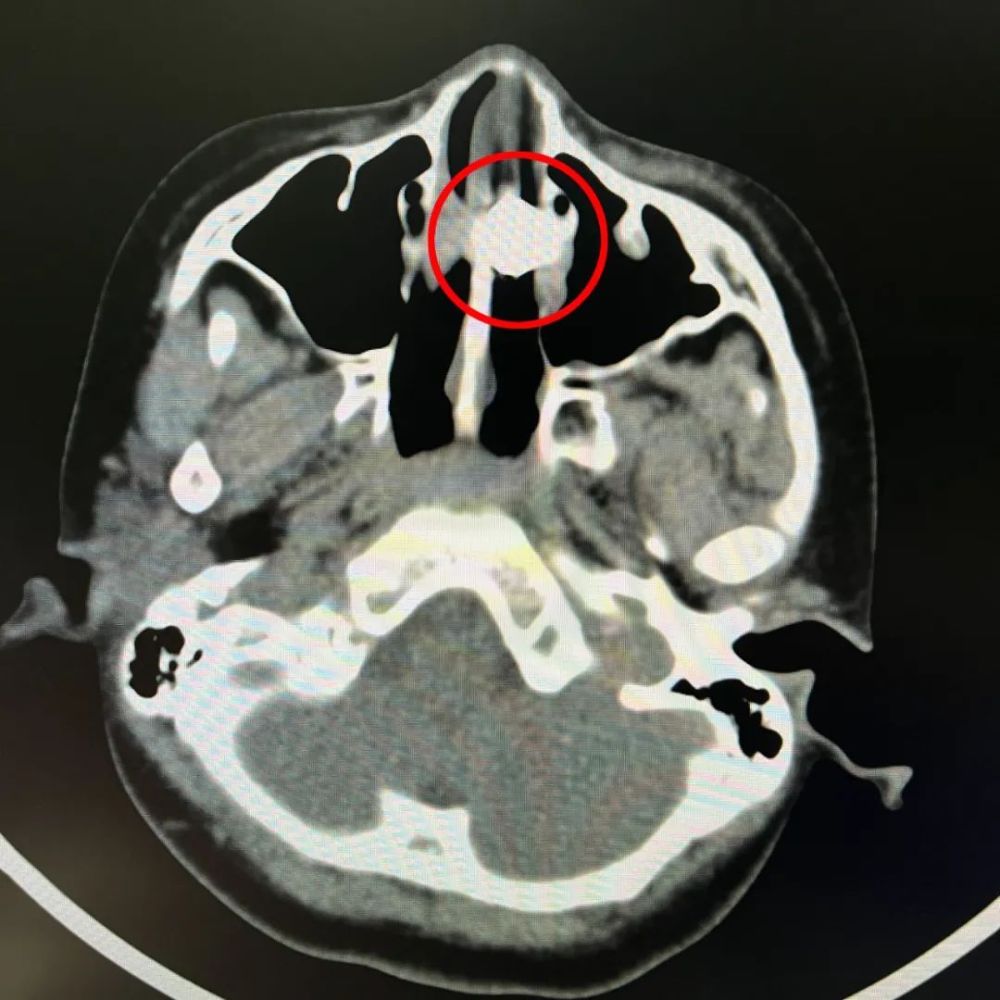

鼻子内部出血较多且面积广泛,同时发现了不明异物